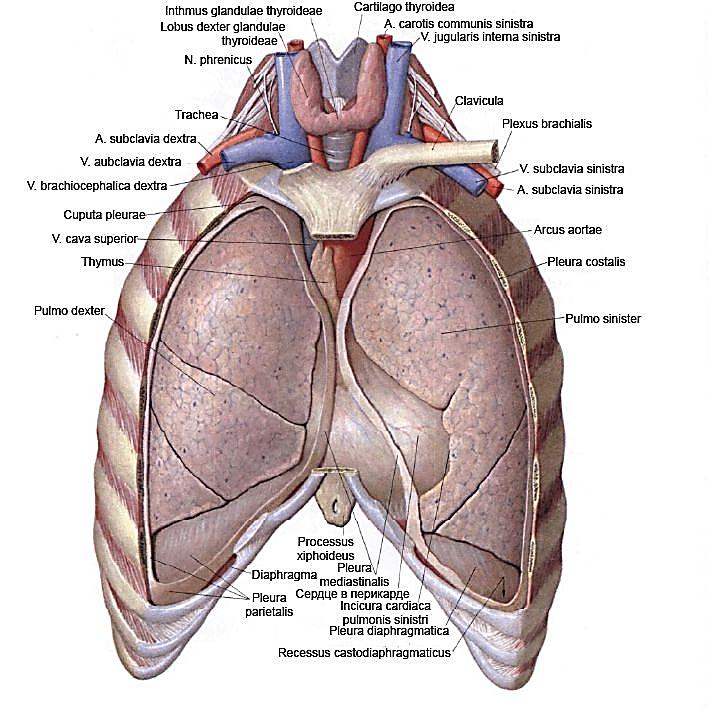

Анатомия Сердца: Расположение и Функции